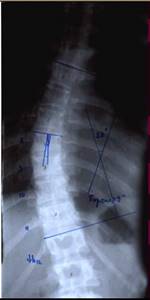

| Больной Т-ов, 16 лет Сколиоз IV степени. До операции |

|

| Внешний вид больного на 10 день после операции |